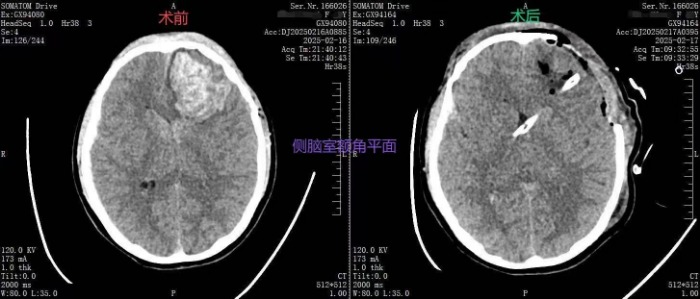

据悉,2月16日晚,一名14岁的学生因头部外伤出现意识障碍,被紧急送往我院。患者入院时处于昏迷状态,呼吸暂停明显,紧急CT检查显示头部多处出血量大,病情极为危急,若不立即抢救,患者随时可能面临生命危险。情况十分紧急,家属焦虑万分。

在手术过程中,团队成员张志涛、刘汪旺首次运用改良潘氏点穿刺脑室技术,在神经内镜提供的清晰视野下,进行了精准的操作。他们凭借丰富的临床经验和精准的操作技巧,迅速完成手术,成功避开了语言中枢,通过单一入路解决了脑内及脑室内血肿清除的两大难题,彻底清除了血肿,成功解除了患者的生命威胁。

手术后,患者意识恢复良好,四肢活动自如,能够正常说话,生命体征稳定。患者家属对医院的救治表示了高度认可,并对医护团队的辛勤付出表示了诚挚的感谢。